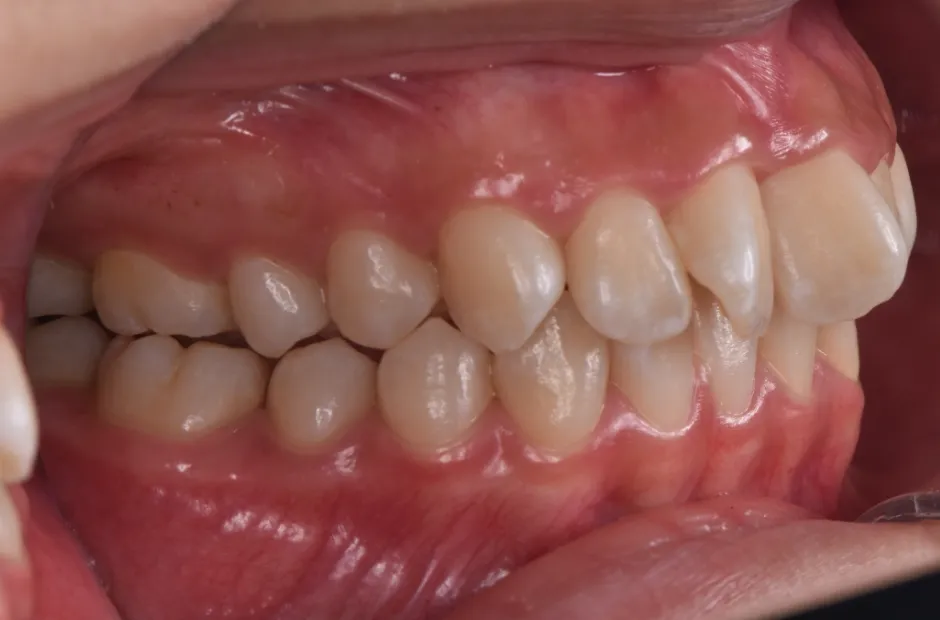

治療症例

ブラケット矯正

前歯部反対咬合

| 診断名・主訴 | 前歯部反対咬合 |

|---|---|

| 年齢・性別 | 14歳・男性 |

| 治療期間・回数 | 1年2か月 |

| 治療に用いた主な装置 | ブラケット矯正 |

| 抜歯部位 | なし |

| 治療費 | 60万円(税抜) |

| リスク・副作用 | 装置による違和感・疼痛・歯肉退縮・歯根吸収・虫歯のリスクなど |

治療後